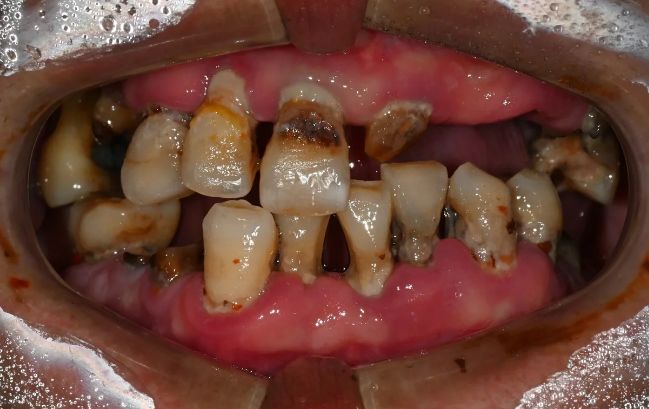

2022-02-03

2022-06-0750대 남성, 원데이 수면 전체 임플란트 19개 식립